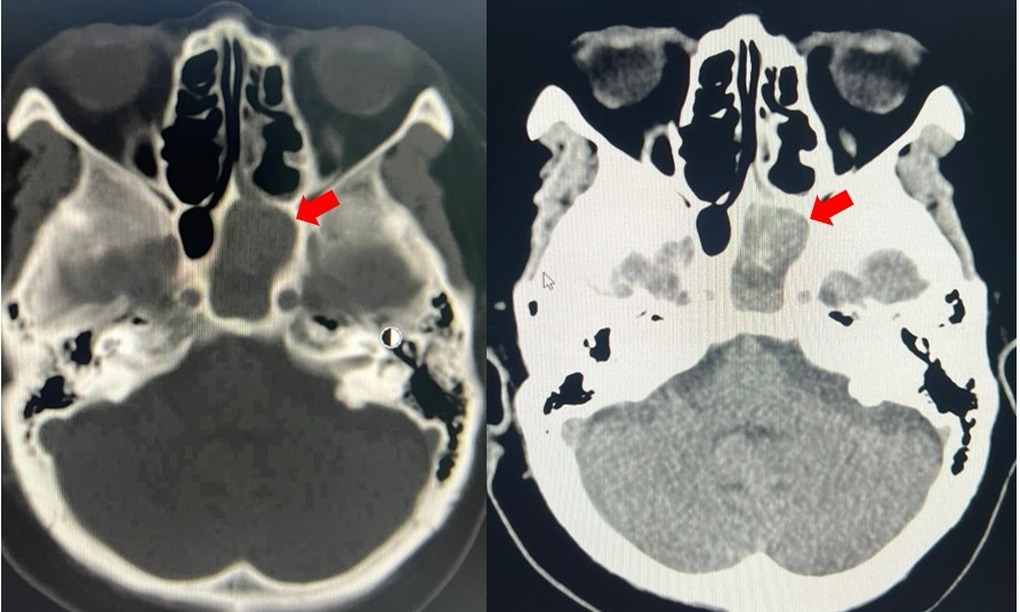

Kết quả chụp CT scan và cận lâm sàng sau đó cũng xác định người bệnh mắc viêm xoang bướm trái do nấm kèm tình trạng nhiễm trùng. Bên cạnh đó, bà cũng được ghi nhận mắc nhiều bệnh nền như tăng huyết áp, bệnh thận mạn giai đoạn III, đái tháo đường type 2.

Hình ảnh khối nấm xoang bướm bên trái (mũi tên đỏ) (Ảnh: BV).